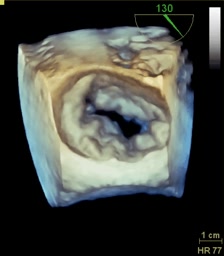

Endocardite della valvola aortica

Daniela Torta